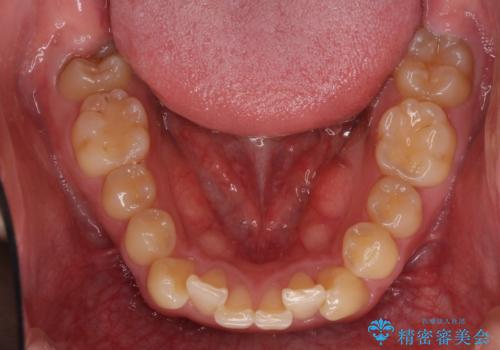

- 上顎の八重歯と前歯のデコボコを気にして来院された患者様です。

八重歯の移動量が多く、インビザライン単体での治療は困難と判断し、補助装置により八重歯移動後にインビザラインを用いることとしました。